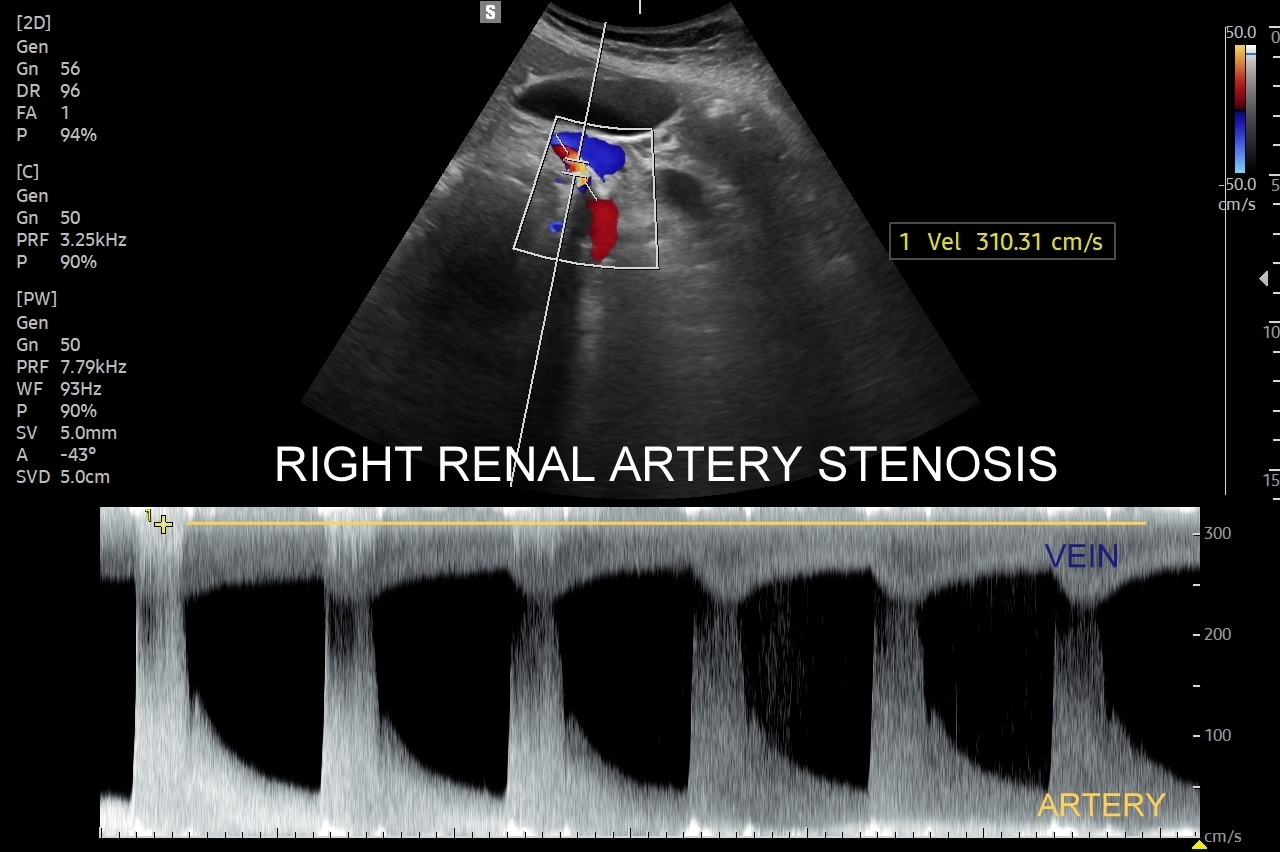

Doppler przepływów nerkowych (USG przepływy nerkowe) jest połączeniem badania obrazowego USG z badaniem funkcjonalnym nerki, jej naczyń tętniczych i żylnych oraz globalnie stanu układu krążenia. Najczęstszym wskazaniem do wykonania USG Doppler tętnic nerkowych, będącego częścią USG Doppler przepływów nerkowych, jest nadciśnienie tętnicze i poszukiwanie jego przyczyn w postaci zwężenia tętnic nerkowych, które mogą wystąpić w odcinku przednerkowym, jak i wewnątrznerkowym. Wykonanie oceny dopplerowskiej nerki jest szczególnie ważne w przypadku wystąpienia nadciśnienia tętniczego u osób młodych lub u dzieci.